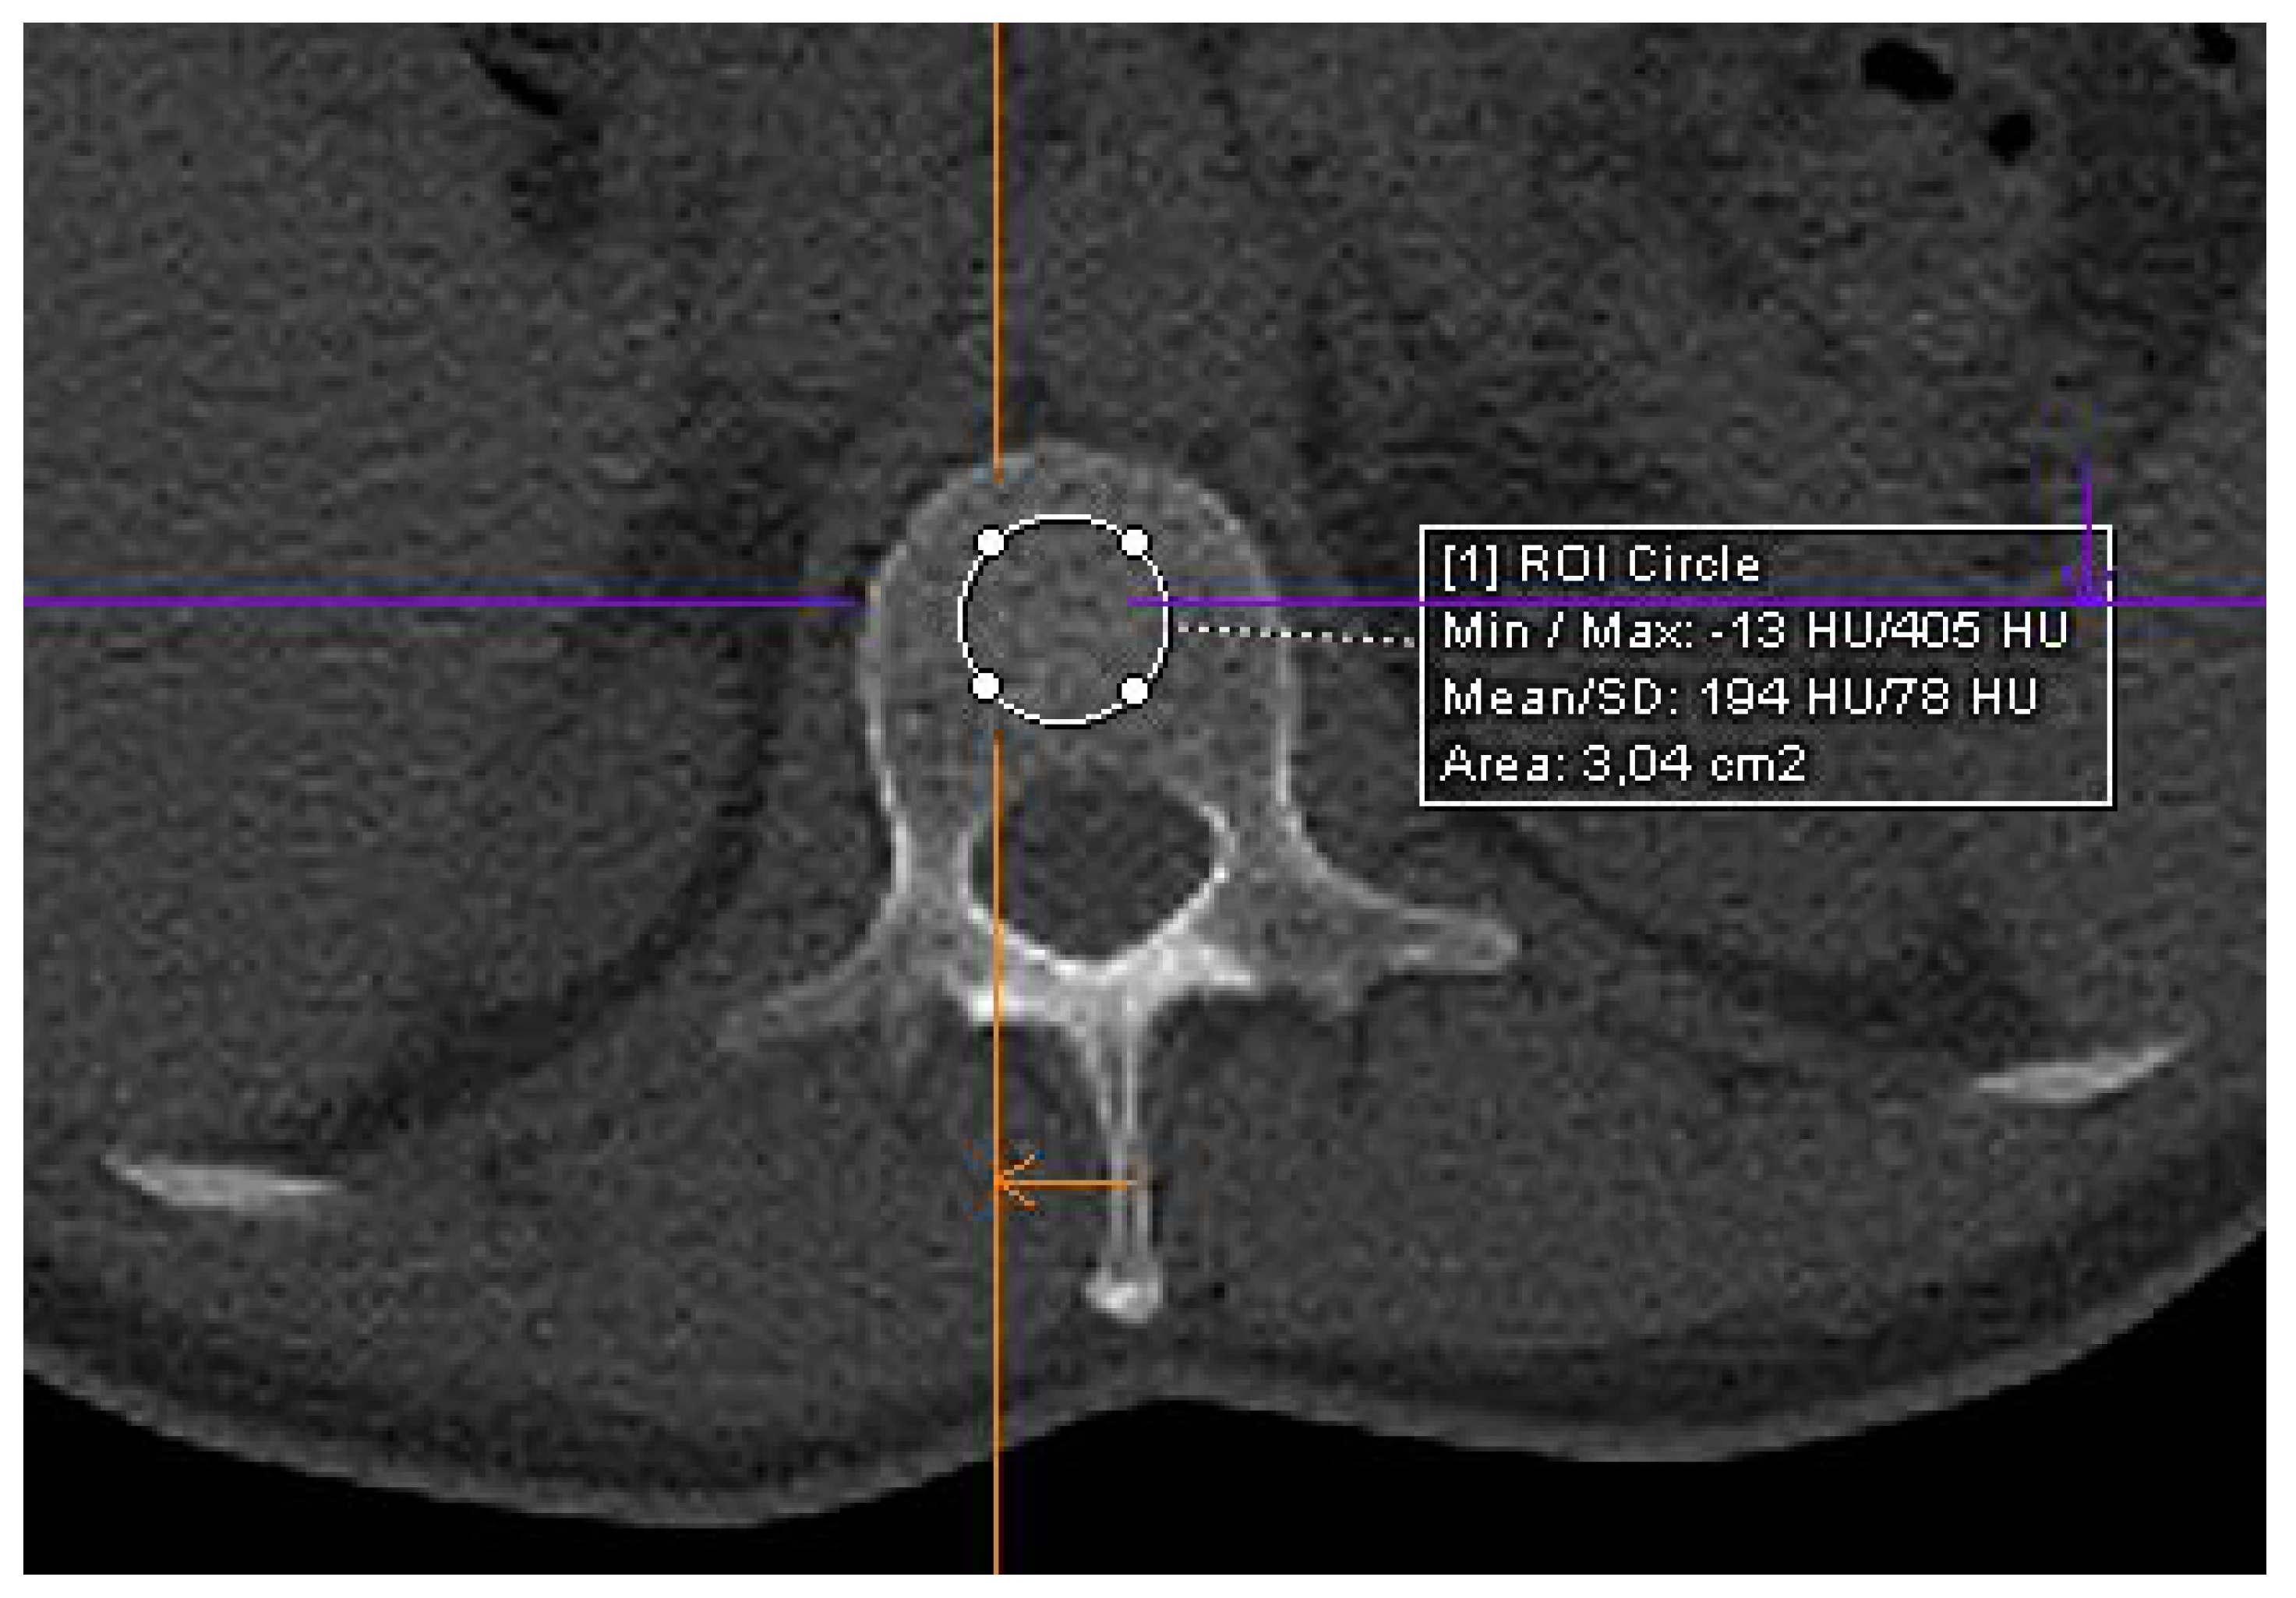

2.4. CT Imaging

3.2. Distribution of Patient Characteristics According to HU